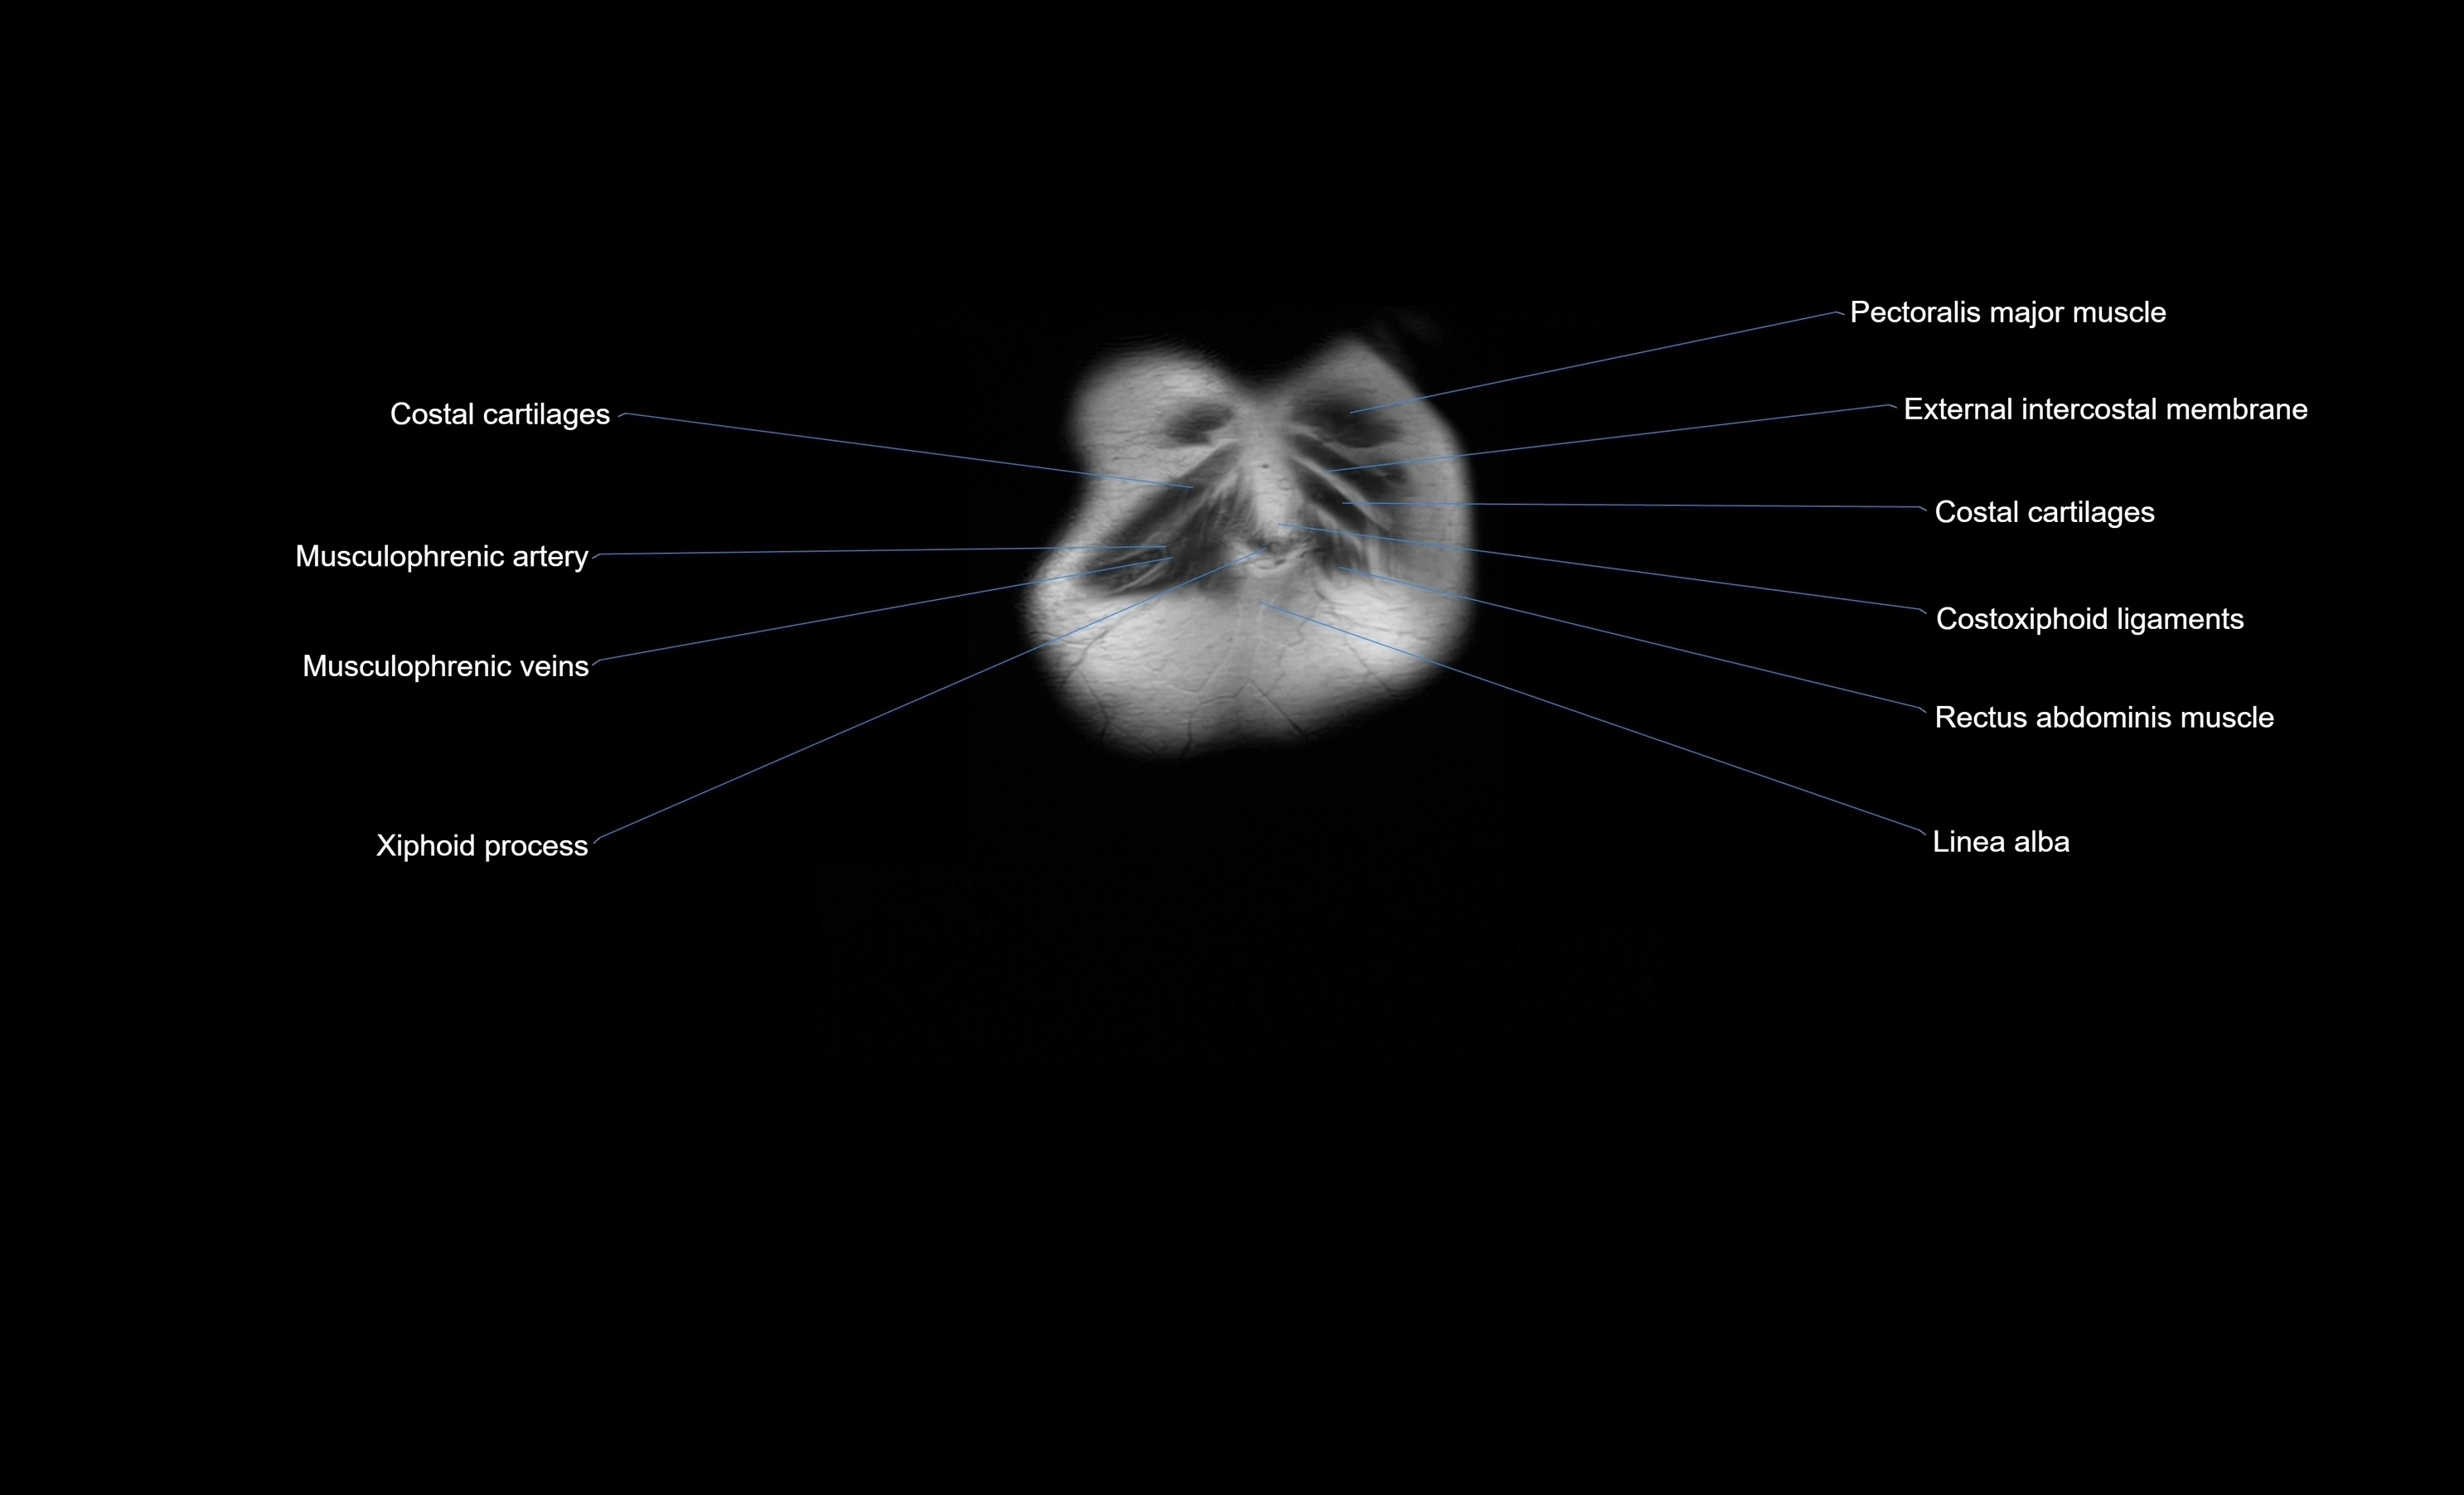

MRI images